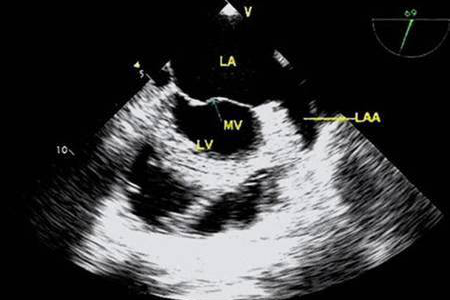

您好!与普通的胸部超声相比,TEE探头直接贴近心脏后方扫查,明显缩短了探头与心脏及其周围大血管的距离,同时也不受肋骨、胸骨、肺及皮下脂肪的干扰,因此图像更清晰,尤其对于心脏后部结构,如对房间隔、主动脉瓣、二尖瓣、左心耳及胸主动脉等结构的显示更具有优势。

1.心律失常:对于房颤、房扑、房速患者了解左心耳血栓,房颤患者做射频消融术前了解左心房及左心耳是否有血栓形成,可以减少手术并发症。

3.心脏瓣膜病:术前可以清晰评估瓣膜的病变程度,术后人工瓣膜功能的评估,有无血栓、血管翳的形成及卡瓣的情况。

7.介入手术应用:左心耳封堵术、各个瓣膜球囊扩张、经导管主动脉瓣置入术等。